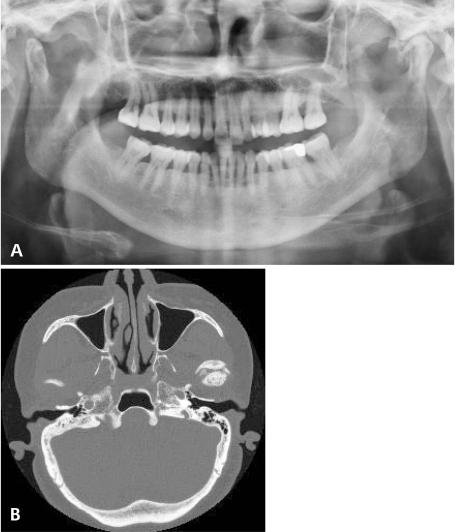

颅面部骨瘤

Osteomas of the craniofacial region.

A retrospective study of 18 patients diagnosed with osteomas in the craniofacial region was performed. The age, gender, location, symptoms, and the radiological findings were recorded.

RESULTS

There were 13 women and 5 men from 18 years to 69 years of age (mean age, 42±27 years). Fourteen osteomas were found in the mandible (78%), two in frontal sinus, one in sphenoid bone, and one in maxilla.

结果

18例患者中,女性13例,男性5例,年龄18岁至69岁(平均年龄42±27岁)。14例骨瘤位于下颌骨(78%),2例位于额窦,1例位于蝶骨,1例位于上颌骨。